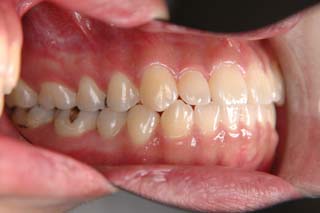

(叢生/顎関節症/上顎左側小臼歯抜歯)

左側の臼歯部干渉が、治療を通じてみられたので、オーバーコレクション気味に軽い臼歯部開咬にしてあります。咬合器上での顎位の偏位はかなり軽減し、頭頚部の症状も随分軽快したようです。歯列の改善と、顎関節症状には、なんだかの関連があると推測されますが、不明なことが多いです。